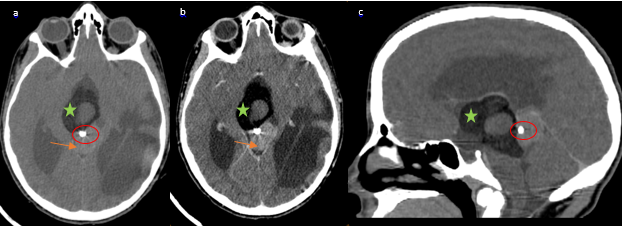

A 12-year-old male patient with a 2 months history of intermittent headaches, presented with acute onset nausea, headache, and projectile vomiting while sitting at school. After seeking medical attention, he was found to be neurologically intact on physical exam. CT scan of the head was performed and demonstrated a mixed density mass in the pineal region with central calcifications, and soft tissue components (Figure 1). Hypodense lesions were seen in the lateral ventricles, third ventricle, and quadrigeminal cistern. The lesions in the lateral ventricles demonstrated hypo attenuations as low as -93 Hounsfield Units, consistent with fat with frontal horn level (Figure 2 & Figure 3). Ventriculomegaly was also evident, due to the obstruction of the aqueduct of Sylvius.

Figure 3 (a) NECT in axial view and postcontrast coronal (view) (B) show hydrocephalus secondary to the obstruction of the aqueduct of Sylvius by the pineal teratoma.